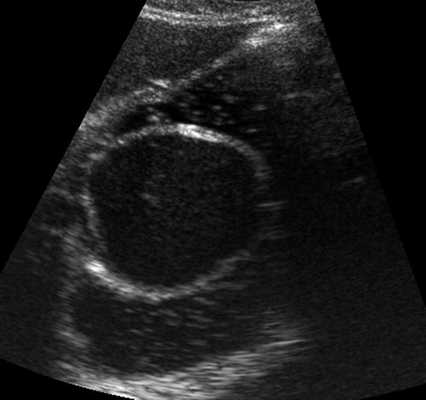

Однако есть важное отличие этих энтерогенных кист от кист яичника

- особое строение стенки энтерокистомы, содержащей элементы кишечной стенки: цилиндрический эпителий, Либеркюновы железы, ворсинки, гладкие мышечные волокна. Именно это отличие строения стенки кисты замечательно регистрируется с помощью методики УЗИ (см. фото).

Энтерокистомы часто остаются соединены с кишкой посредством тонкого соединительнотканного тяжа, их содержимое - негомогенное, иногда слоистое - слизь, холестерин, отторгнутый эпителий, что создает особенную УЗИ-картину.